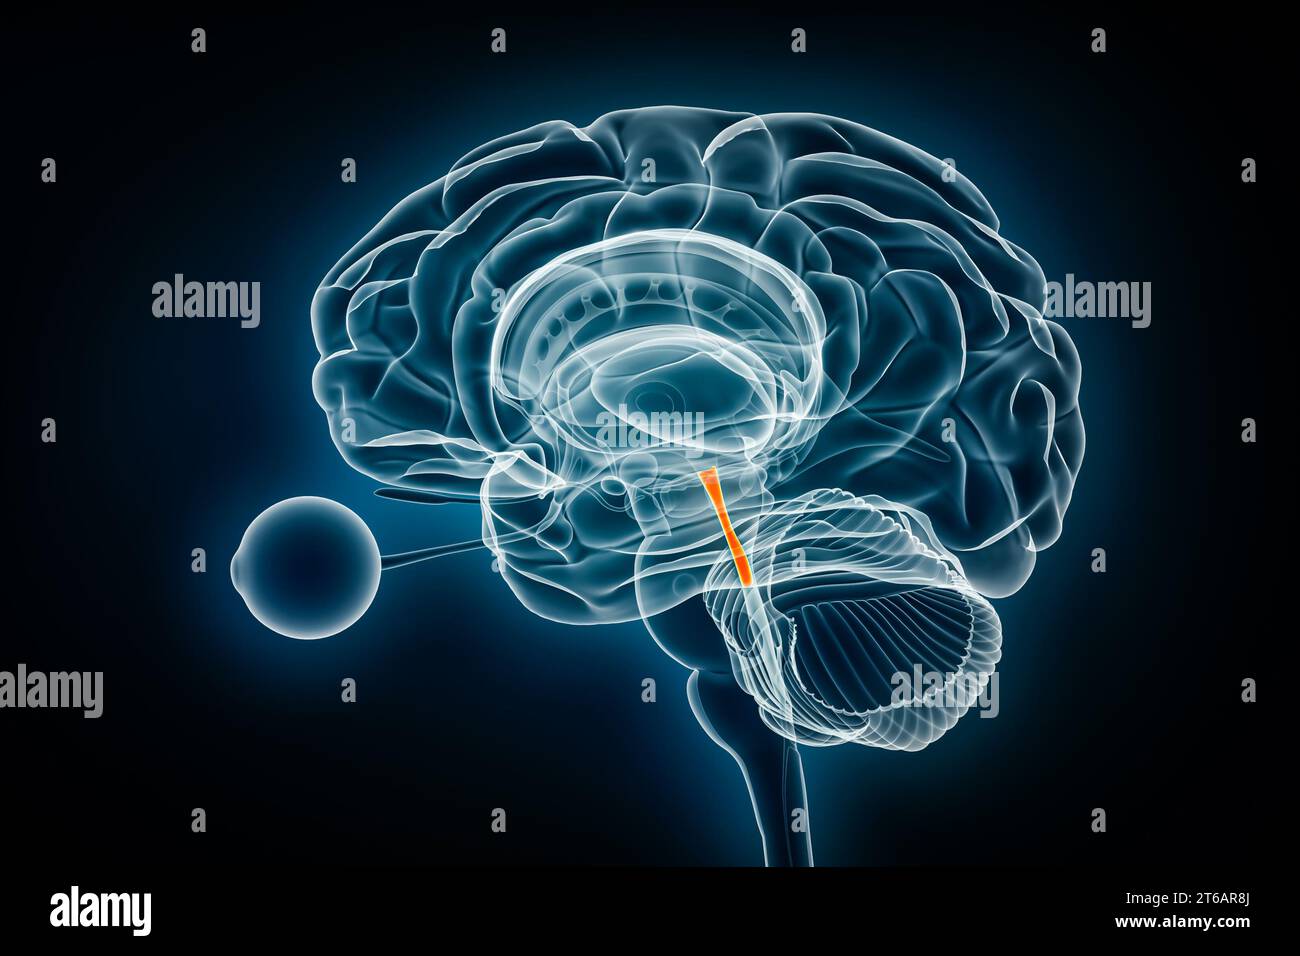

RF2T6AR8J–3D-Rendering-Illustration für die Röntgenansicht des Gehirns oder des Sylvius aquädukt. Anatomie des menschlichen Gehirns und des Ventrikelsystems, Medizin, Gesundheitswesen, Biologie, Wissenschaft,